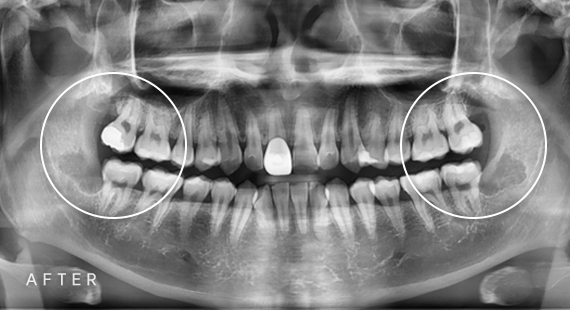

임플란트

충치치료

신경치료

사랑니 발치